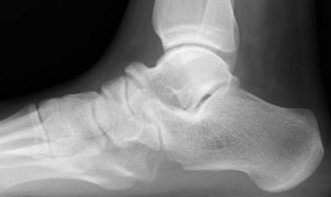

Xray

| Talar beaking | C Sign | Harris axial view | Ball and socket ankle joint |

|---|---|---|---|

| Traction spur due to increased stress | Medial outline talar dome and posterior sustenaculum tali |

40 degree axial view Ski jump view Visualize middle facet |

Secondary to rigid subtalar joint Develops to allow inversion / eversion |

Talar beaking with C sign